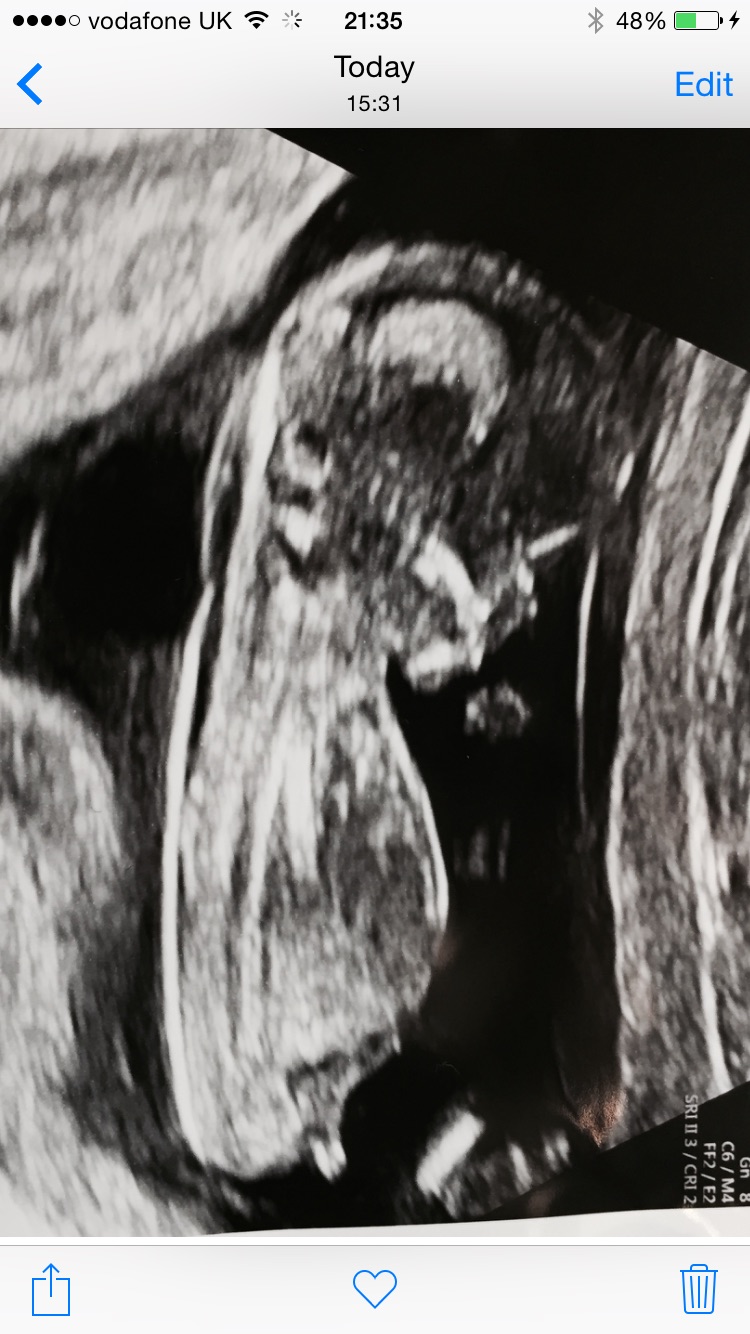

Does anyone have a clue what I'm having (other than a baby!)...

Attachment 24271Attachment 24272

Maybe Girl if 13 weeks or more :)

Was 13+ 1 at the time

I would guess girl :)

Guessing girl :)

Girly lean.

Boy lean due to slight angle from me.

This is a hard one! Boy lean as slightly raised and quite a short nub X